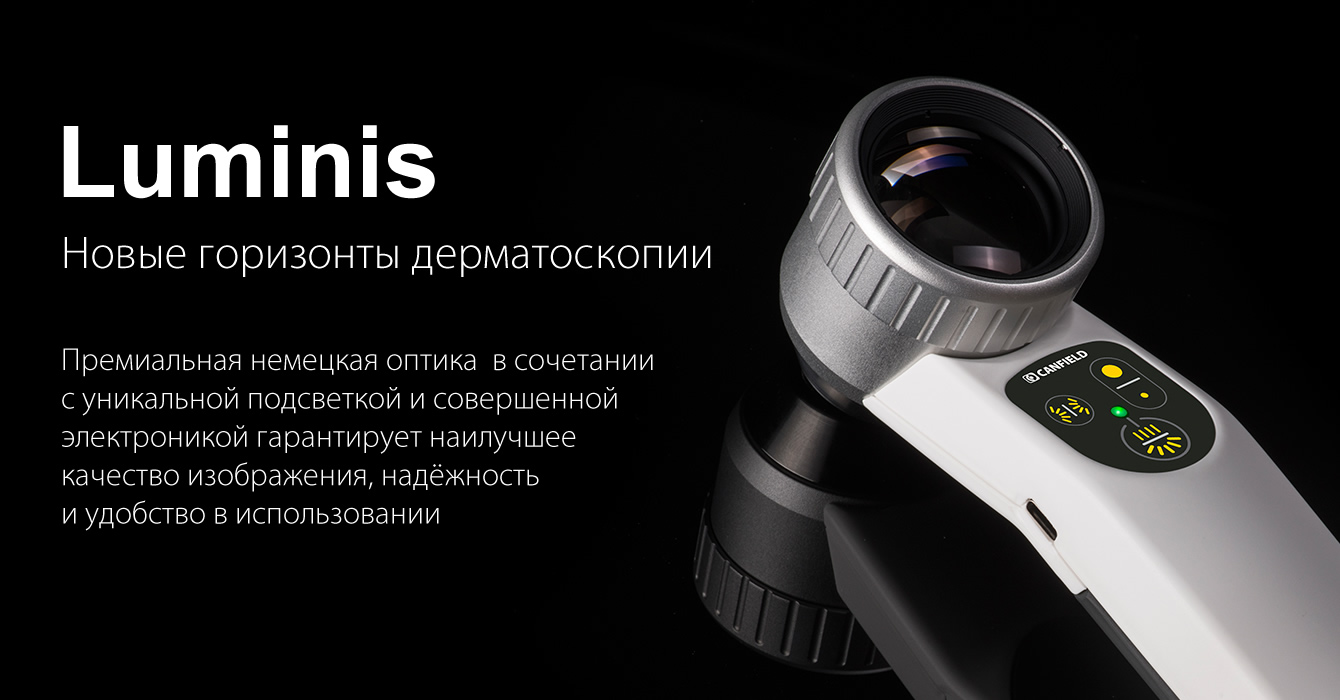

Дерматоскоп оптический "Люминис"

Высококачественный дерматоскоп с самым широким полем обзора

Дерматоскоп оптический Canfield®, вариант исполнения "Люминис" (Luminis) *, Германия, является высокотехнологичным медицинским изделием для дерматологических осмотров поверхности кожи с целью исследования и диагностики различных патологий, включая пигментные новообразования, предраковые и раковые заболевания кожи, васкулярные нарушения, паразитарные инфекции и многое другое. Дерматоскоп "Люминис" снабжён самой широкой в своём классе многоэлементной ахроматической оптической линзой диаметром 37 мм с 10-кратным увеличением. Эта линза производится в Германии с традиционно первоклассным качеством и даёт точнейшие изображения, в которых отсутствуют любые графические и цветовые искажения. Широкая оптическая линза позволяет производить осмотр, даже не наклоняясь слишком близко к пациенту, а с некоторого расстояния. Получению прекрасных дерматоскопических изображений способствует непревзойдённое качество светодиодной подсветки, которой управляет микроконтроллер. Подсветка даёт как обычный неполяризованный, так и поляризованный свет. Осмотрам помогают такие функции, как боковая подсветка слева или справа, выявляющая текстуру и рельеф, и двухступенчатый регулятор силы света. Дерматоскоп "Люминис" реализует уникальные преимущества трёх методов дерматоскопии – бесконтактного поляризованного (без применения иммерсионных жидкостей), контактного поляризованного и контактного неполяризованного (с применением иммерсионных жидкостей) – в одном приборе инновационной конструкции. Дерматоскоп "Люминис" отличается высокой эргономикой, легко управляется одной рукой, имеет небольшой вес. Питание подсветки осуществляется от внутренней аккумуляторной батареи. При перерывах в работе "Люминис" можно ставить в настольную подставку, снабжённую контактами для подзарядки, – так он всегда будет под рукой и постоянно готов к использованию. "Люминис" – это исключительно удобный, функциональный и высокоэффективный оптический дерматоскоп для современной практической работы врачей тех специальностей, которые связаны с диагностикой и лечением патологий кожи.

Удобная панель кнопок

Удобная кнопочная панель управления облегчает работу одной рукой.

Естественная подсветка

Кросс-поляризованная и неполяризованная подсветка.

Сменные рабочие наконечники

Практичные наконечники на магнитном креплении заменяются за 3-5 секунд.

Эргономичный дизайн

Широкое поле обзора позволяет производить осмотр с расстояния до 20 см.

10-кратное увеличение

10-кратное увеличение и высокая чёткость без искажений по всему полю обзора.